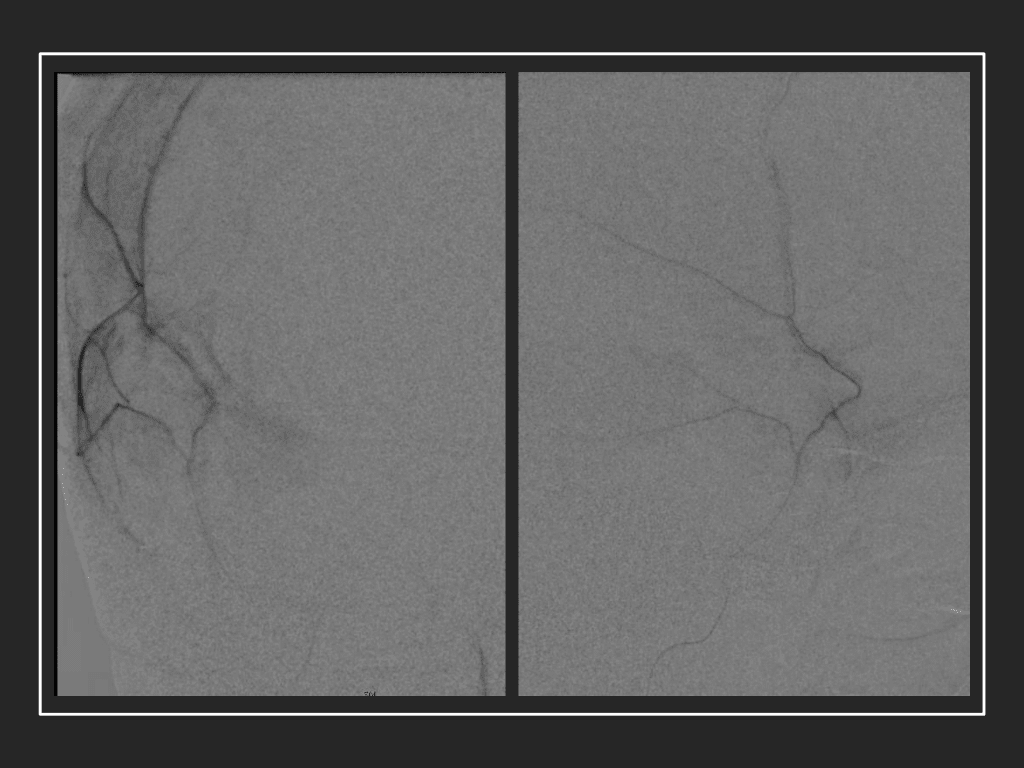

Figure 8. Dense contrast staining of vascular membranes during embolization.

Care must be taken to place the microcatheter within a safe position for embolization, with special attention to potential collateral branches to the orbit/eye via sphenoid or meningo-lacrimal branches (which may cause vision loss) or petrosal branches supplying the geniculate ganglion, the tympanic portion of the facial nerve, and often the trigeminal nerve via a branch coursing along the greater petrosal nerve. Once a safe position in the main trunk of the MMA, or superselectively in each of its divisions is achieved, embolization is performed until stasis of contrast and dense contrast staining of the dura is observed within the embolized vascular beds.7

Although conventional surgical methods, such as burr hole irrigation or observation in asymptomatic or minimally symptomatic patients have been the mainstay of treatment, middle meningeal artery (MMA) embolization has emerged as a promising adjunctive or alternative treatment. MMA embolization is a neuroendovascular technique which involves placing a microcatheter into the Middle Meningeal Artery, most commonly on the side of the cSDH (occasionally, bilateral embolization has been recommended for larger or bilateral collection. Embolization of both the anterior (frontal) and posterior (parietal) division is performed using a variety of embolic materials (liquid NBCA, Onyx, coils), although polyvinyl alcohol particles of <250 microns are most commonly used to achieve distal penetration and occlusion of the pre-capillary and capillary beds. The micro-leakage of blood and transudative proteinaceous inflammatory fluid in these inflammatory membranes is creating an imbalance in cycle of resorption and preventing resolution or promoting recurrence or growth of these cSDH collections and associated mass effect and midline shift.